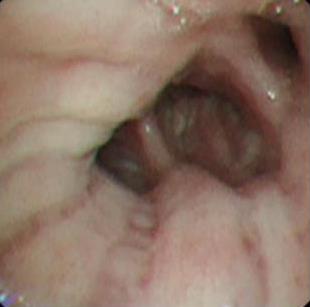

• 侵袭性肺真菌病的支气管镜表现及介入治疗效果

2025, 31(9):81-90. DOI: 10.12235/E20250317

摘要 (112) HTML (56) PDF 6.06 M (77) 评论 (0) 收藏

摘要:目的 探讨侵袭性肺真菌病(IPFD)的支气管镜表现,并评估介入治疗的安全性和疗效。方法 回顾性分析2018年5月12日-2025年5月12日于该院行支气管镜检查的35例IPFD患者的临床资料,观察IPFD的支气管镜表现及介入治疗效果。结果 共收集35例患者临床资料。其中,男22例,女13例,患者年龄(53±14)岁。基础疾病包括:血液系统恶性肿瘤10例,长期应用糖皮质激素者5例,2型糖尿病者4例,肺部恶性肿瘤2例,器官移植1例。胸部CT显示:肺部病变累及单肺叶者19例,累及多肺叶者16例。支气管镜下表现主要为:黏膜充血水肿29例(82.9%)、坏死物堵塞管腔22例(62.9%)、大量黏稠脓性分泌物17例(48.6%)、支气管部分狭窄或闭塞16例(45.7%)、黏膜坏死9例(25.7%)、黏膜出血5例(14.3%)、真菌球3例(8.6%)。其中,32例(91.4%)接受全身性抗真菌治疗,17例(48.6%)接受支气管镜局部两性霉素B灌注治疗,10例(28.6%)采用活检钳钳除病灶,6例(17.1%)采用冷冻探头冻取病灶,4例(11.4%)接受氩气刀治疗。28例(80.0%)临床症状明显改善,肺部影像学病灶缩小或消退;4例(11.4%)病灶稳定;3例(8.6%)未完成治疗。结论 IPFD多见于免疫抑制宿主,支气管镜常表现为:坏死物堵塞管腔、伴脓性分泌物、支气管管腔狭窄和局部黏膜充血水肿或坏死。全身抗真菌药物联合支气管镜下介入治疗,安全性高,且疗效好。